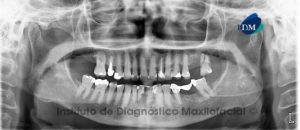

Paciente femenino de 76 años de edad es referido al Instituto de Diagnóstico Maxilofacial (IDM) para evaluación general por presentar enfemedad periodontal avanzada. A la